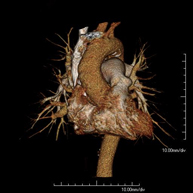

Prueba diagnóstica que consiste en el estudio de la aorta torácica (principal arteria del tórax) mediante el empleo de un equipo de TC (Tomografía Computarizada). Esta técnica requiere el empleo de contraste yodado, y proporciona imágenes de alta definición anatómica. El uso del TCMD (TC Multidetector) acorta el tiempo de exploración, disminuye la dosis de radiación y mejora la calidad de la imagen. Gracias a los múltiples detectores, en determinados estudios se puede acoplar la obtención de la imagen con el latido cardíaco, técnica que permite el estudio de la válvula aórtica y de la raíz de la arteria aorta (primeros centímetros), donde el latido del corazón suele provocar múltiples artefactos de movimiento. - Angio –TC Artèries pulmonars (estudi TEP, Tromboembòlia pulmonar)

Prova diagnòstica que consisteix en l'estudi de l'aorta toràcica (principal artèria del tòrax) mitjançant l'ús d'un equip de TC (Tomografia Computeritzada). Aquesta tècnica proporciona imatges d'alta definició anatòmica. En la majoria de casos és necessari l'ús de contrast iodat. L'ús del TCMD (TC Multidetector) escurça el temps d'exploració, disminueix la dosi de radiació i millora la qualitat d'imatge. Gràcies als múltiples detectors en determinats estudis es pot afegir l'obtenció de la imatge amb el batec cardíac, tècnica que permet l'estudi de la vàlvula aòrtica i de l'arrel de l'artèria aorta (primers centímetres), on el batec del cor acostuma a provocar falses imatges a causa del moviment. - Angio TC d'artèries pulmonars (estudi Tep, tromboembolisme)